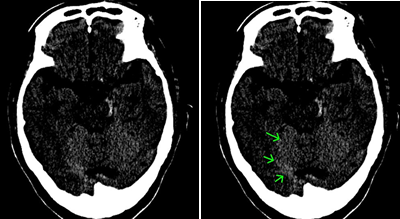

左顔面部を強打した脳挫傷の事例

CT画像では、中央部右側に白い○状の形があるのが読み取れます。これが脳挫傷が生じた部分です。

これは、バイクを運転していたところ、自動車と出合い頭で衝突した被害者のものです。左顔面部を強打し、左下顎骨骨折、左頬骨骨折となり、左下からの突き上げる衝撃で、左側頭葉に局在性の脳挫傷が発症したものです。

左側頭部を強打した脳挫傷の事例

CTの3D画像では骨折線が確認できます。CT画像では矢印のところに異常があります。

自転車に乗っていたところ、軽自動車と出合い頭で衝突した被害者のものです。左側頭部を骨折し、その衝撃により、打撲部位の直下の脳組織が挫滅となりました。これも、局在性の脳挫傷です。